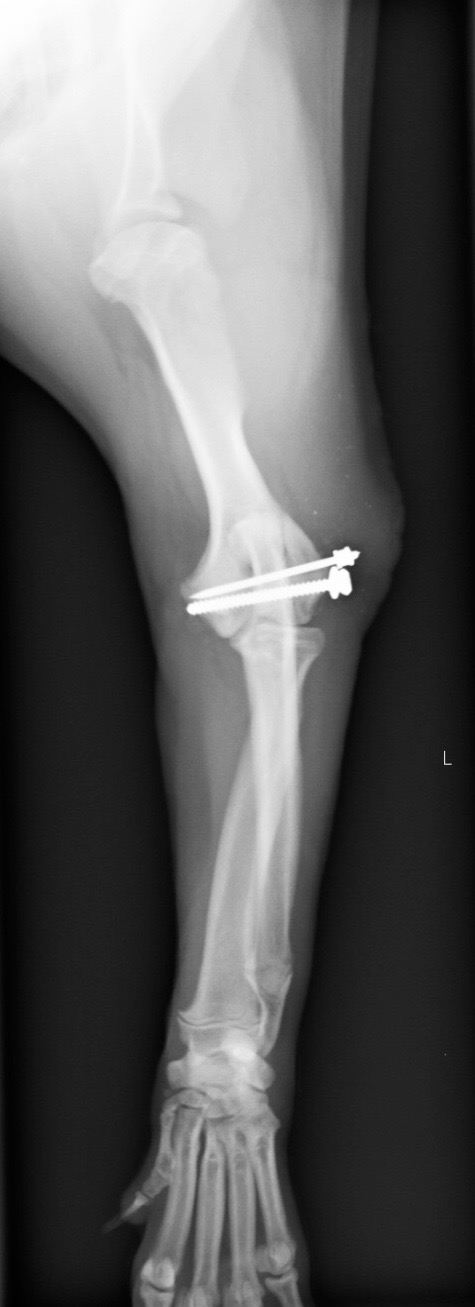

成長版骨折ということもあり早期の手術が必要と判断し、そのまま入院・手術となりました。 肘部の外側からアプローチを行い、肘関節を露出します。 骨折部位を確認し、ピンニングによって仮固定を行います。 Cアームを用いて骨折部位のアライメントが整っているのを確認した後にスクリューを入れていきます。

スクリューとピンの固定後、X線検査にてアライメントが整っているか確認して終了です。